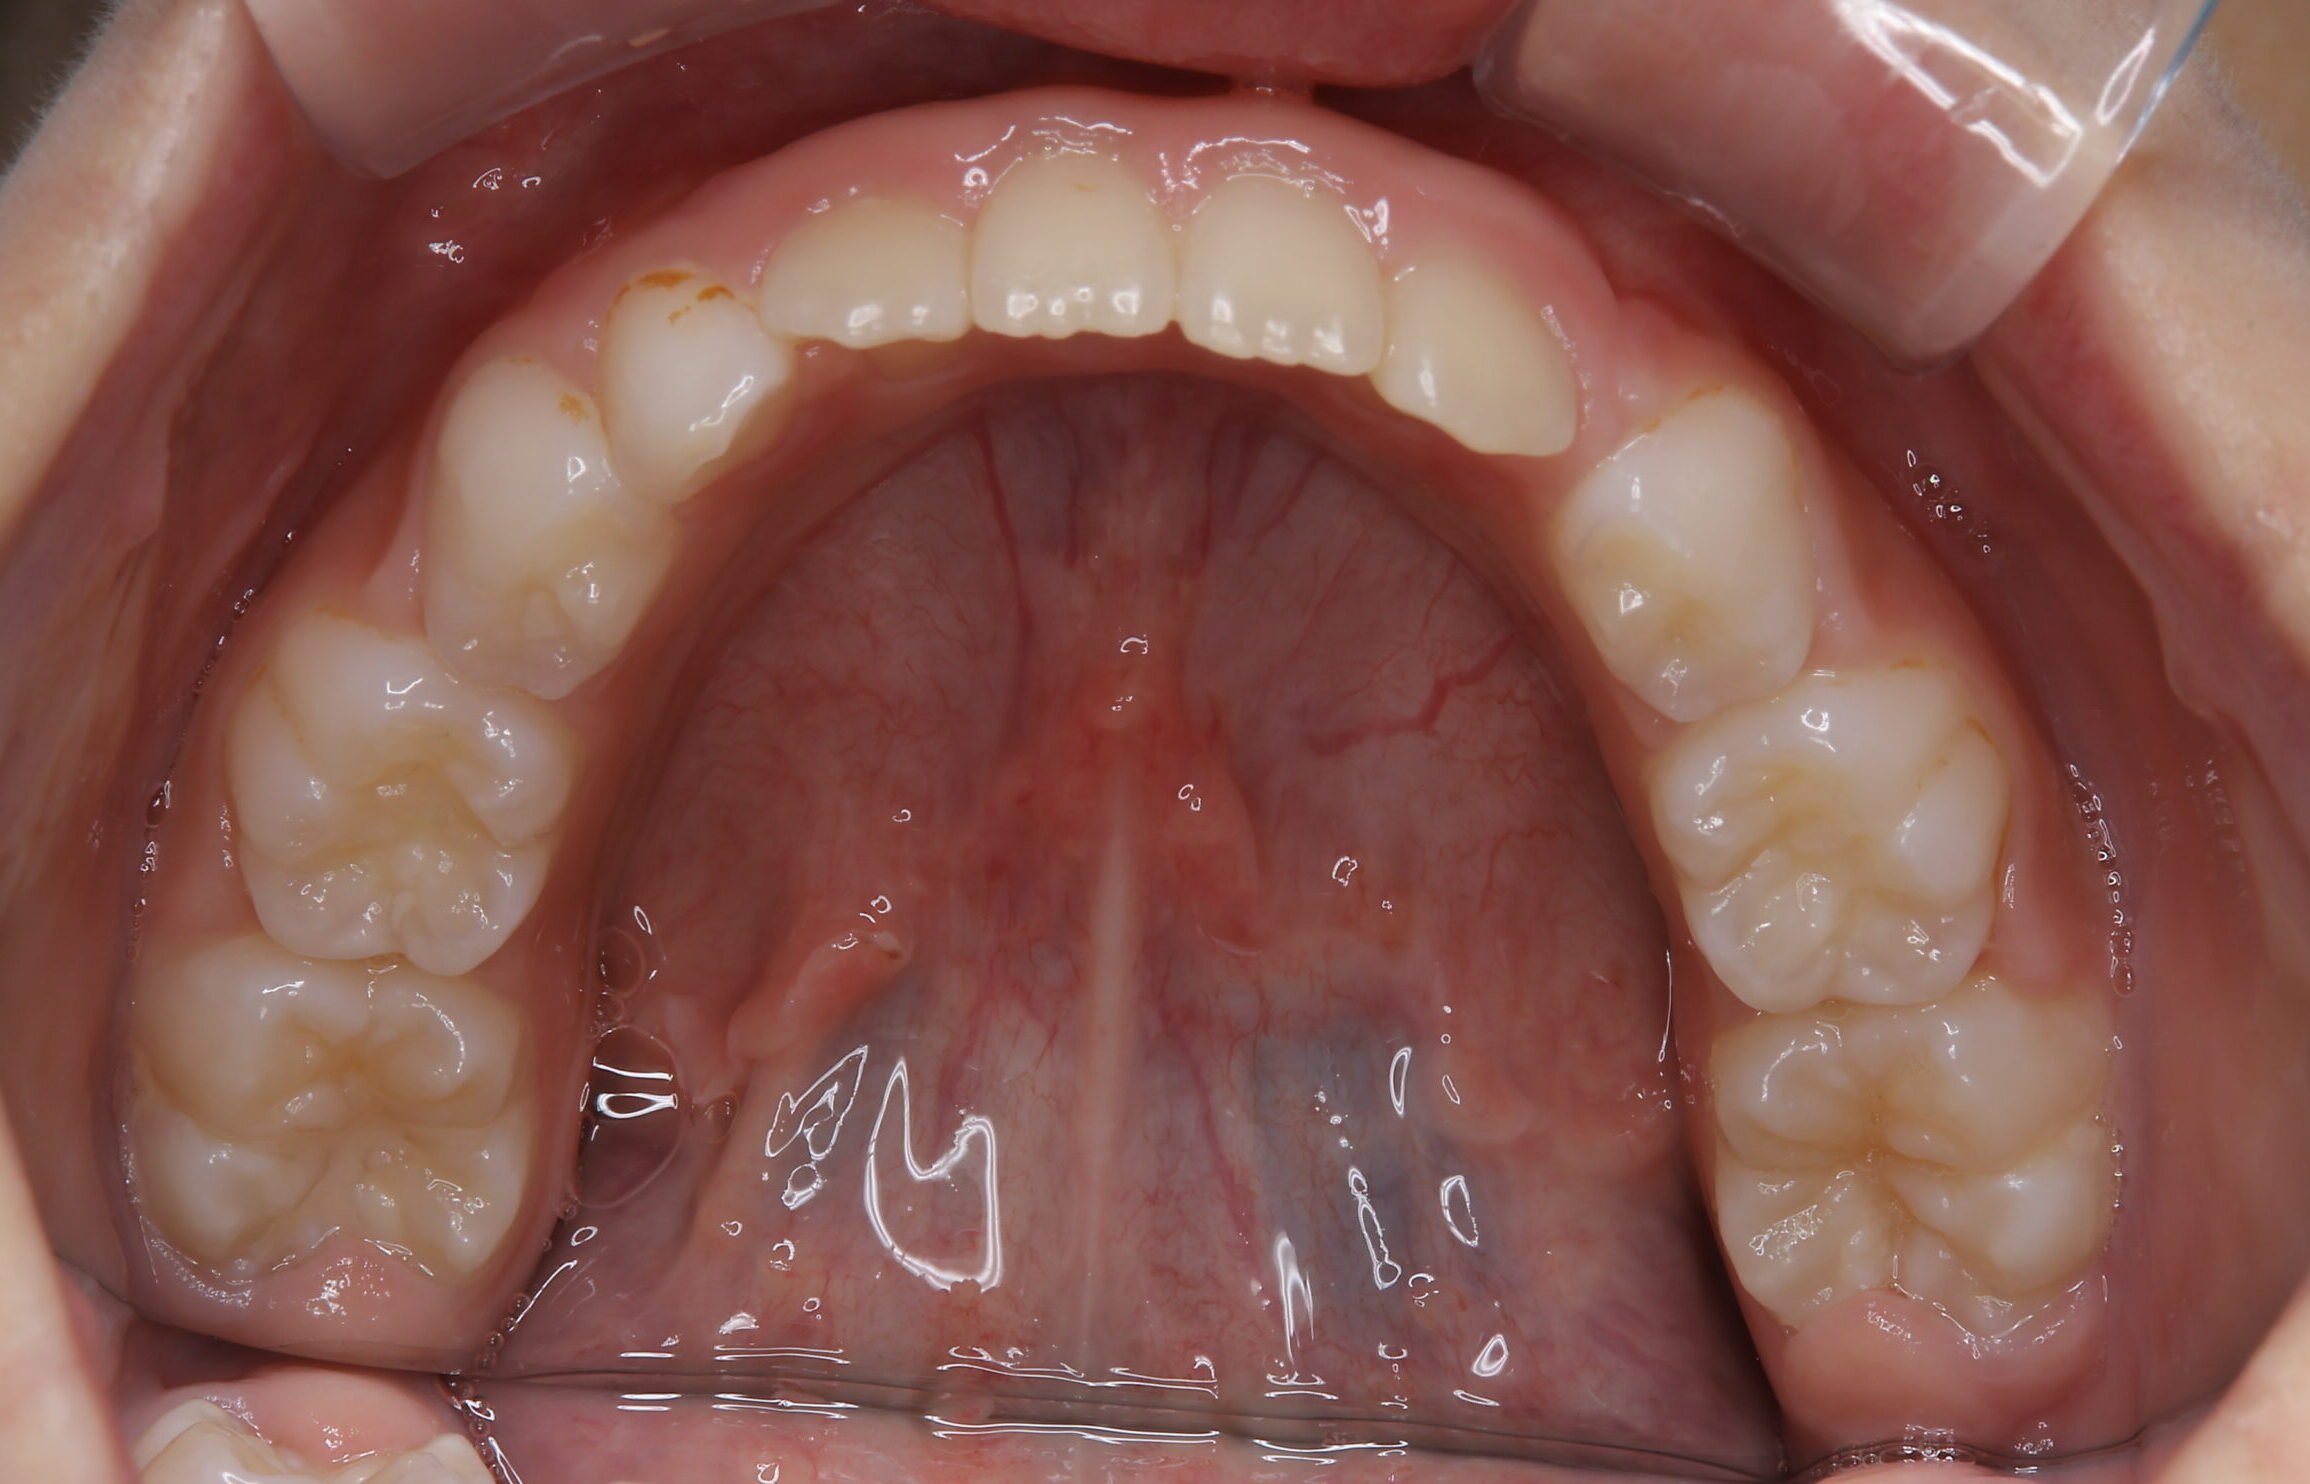

子供の歯のスペースが足りない治療(歯列矯正用咬合誘導装置(マイオブレース)とアクティビティ併用) 子供の歯のスペースが足りない治療(歯列矯正用咬合誘導装置(マイオブレース)とアクティビティ併用)

子供の歯のスペースが足りない治療(歯列矯正用咬合誘導装置(マイオブレース)とアクティビティ併用)